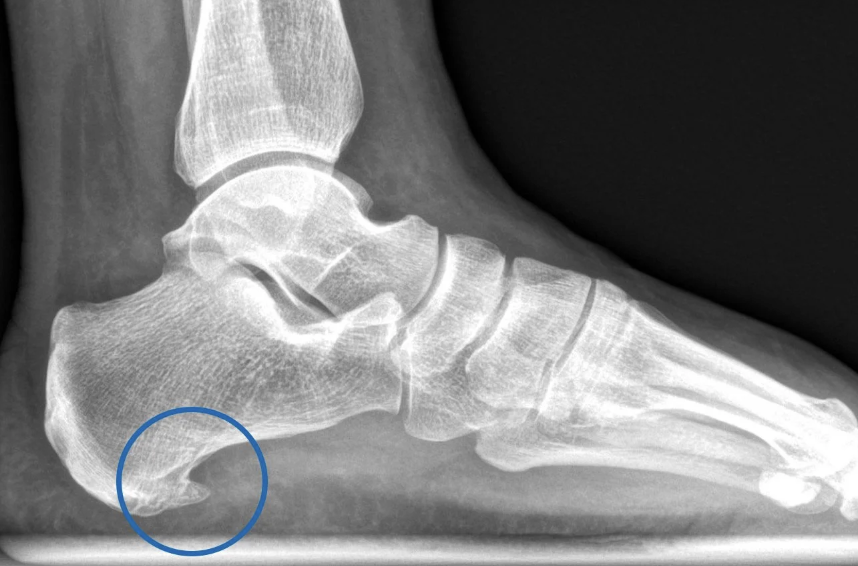

Fascitis plantar

¿Qué es la fascitis plantar?

Inflamación de la aponeurosis plantar en su inserción calcánea

11

Q

¿Qué complicación se observa en fases crónicas?

Espolón calcáneo

Consecuencia de la inflamación crónica de la fascia plantar